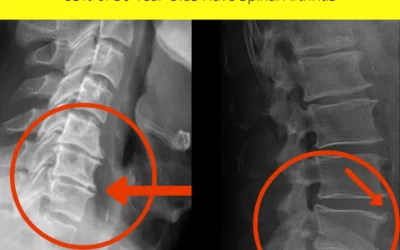

The #1 Cause Of Disability in the U.S.A. is . . .

Did you know that the #1 cause of disability in America is spinal arthritis? Check out these...